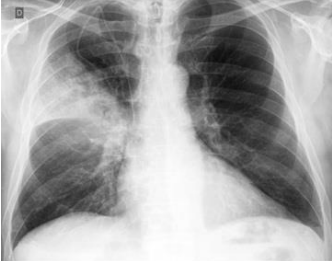

Observe a imagem, a seguir:

Podemos observar, nitidamente, nesta radiografia, um infiltrado à direita, compatível com uma consolidação lobar, o que configura:

Frente ao achado no exame radiográfico, o Pneumologista decide entrar com uma Quinolona. Qual dos fármacos, abaixo, foi prescrito: